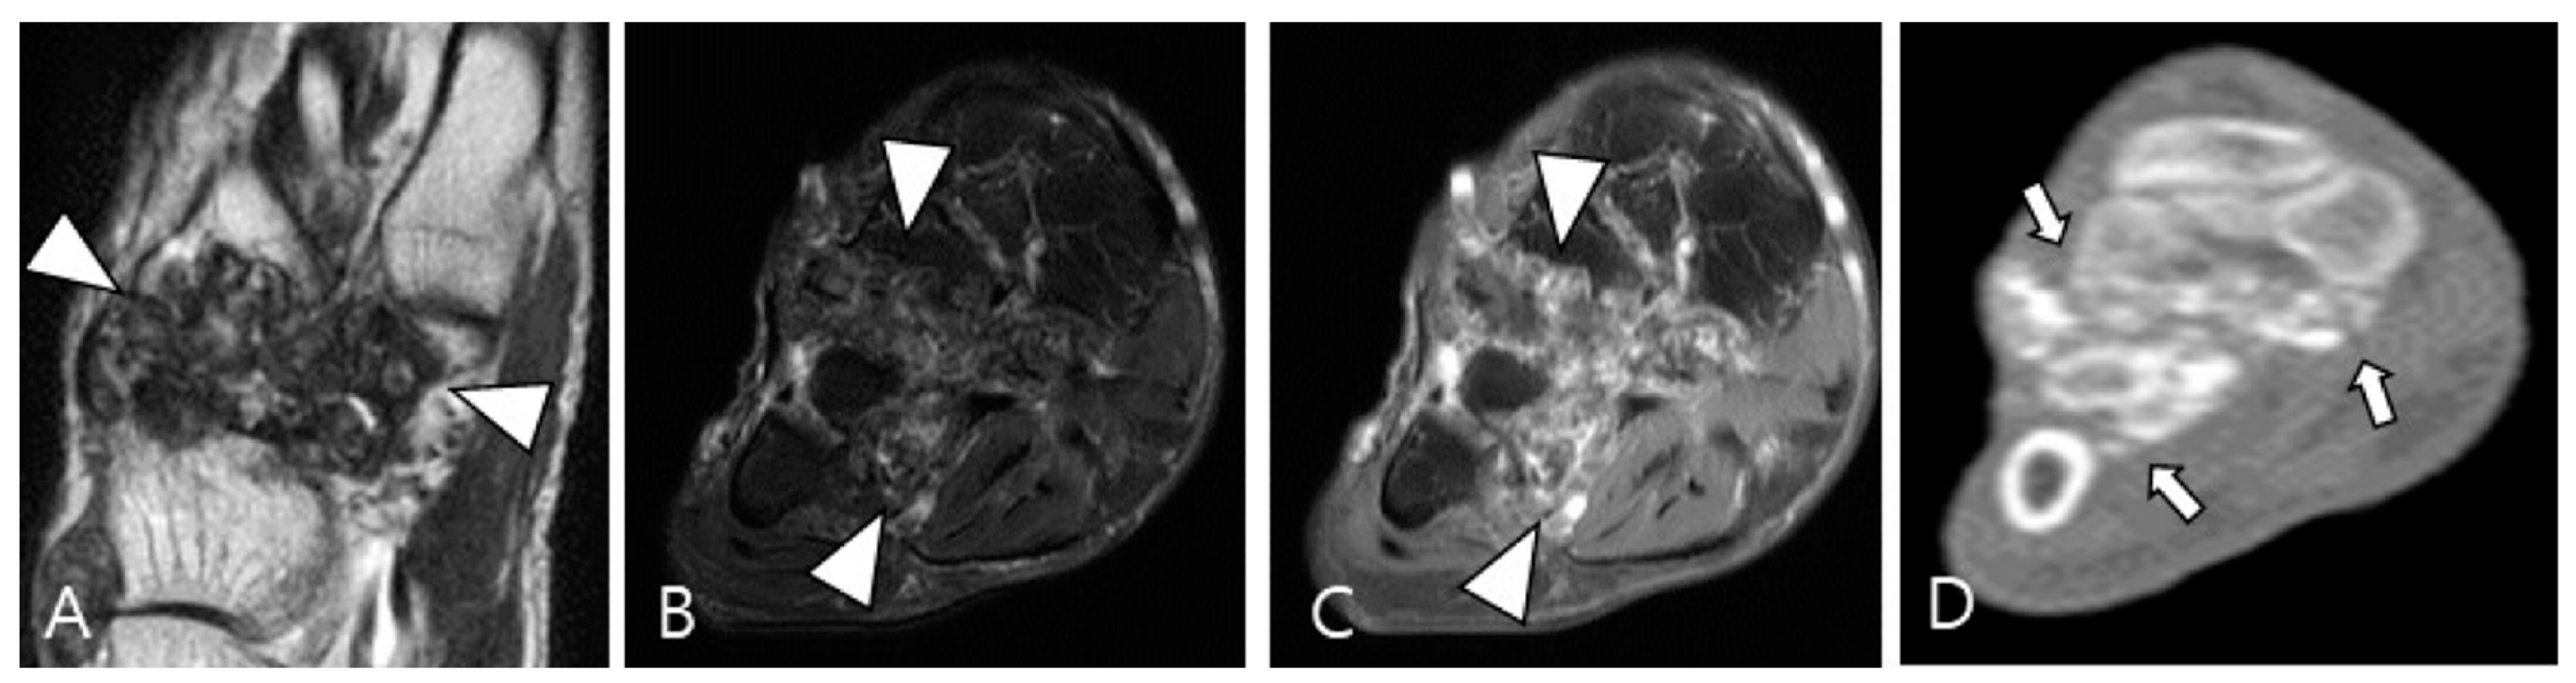

Synovial chondromatosis arises from self-limiting proliferative and metaplastic changes in the synovium [49,53]. It is categorized into primary and secondary forms; the primary form is currently considered a benign neoplastic disease based on cytogenetic analyses, while the secondary form is associated with underlying joint abnormalities such as osteoarthritis, trauma, or previous infectious or inflammatory arthritis [48]. Monoarticular involvement is common, with the knee being the most frequently affected joint, followed by the hip, elbow, shoulder, and ankle [48]. The condition can present as multiple round bodies, similar in size and shape, with MRI revealing these loose bodies amidst synovial proliferation [49,54]. Mineralized loose bodies exhibit low SI on all pulse sequences, while non-mineralized areas show low SI on T1WI and high SI on T2WI, reflecting the increased water content of hyaline cartilage [48]. Plain radiography or computed tomography (CT) is the imaging modality of choice for identifying cartilaginous nodules, which display a cobblestone pattern and varying degrees of calcification (85% is calcified) or ring-and-arc patterns of mineralization (Figure 11) [48,53]. In long-standing diseases, peripheral enchondral ossification or central dystrophic mineralization can develop within the loose bodies [48,53]. The presence of calcification or metaplastic cartilage helps differentiate synovial chondromatosis from D-TSGCT.

Figure 11.

A 54-year-old male with synovial chondromatosis in the foot. (A) Coronal T2WI demonstrates diffusely low SI of synovial thickening at the Lisfranc or Chopart joints (arrowheads). (B) Axial fat-suppressed T2WI reveals infiltrative soft-tissue extension into the surrounding bone and muscles (arrowheads). (C) Axial contrast-enhanced fat-suppressed T1WI shows minimal peripheral enhancement (arrowheads). (D) Axial CT reveals multiple small conglomerated calcifications in involved tarsometatarsal joints (arrows) with bony erosion.